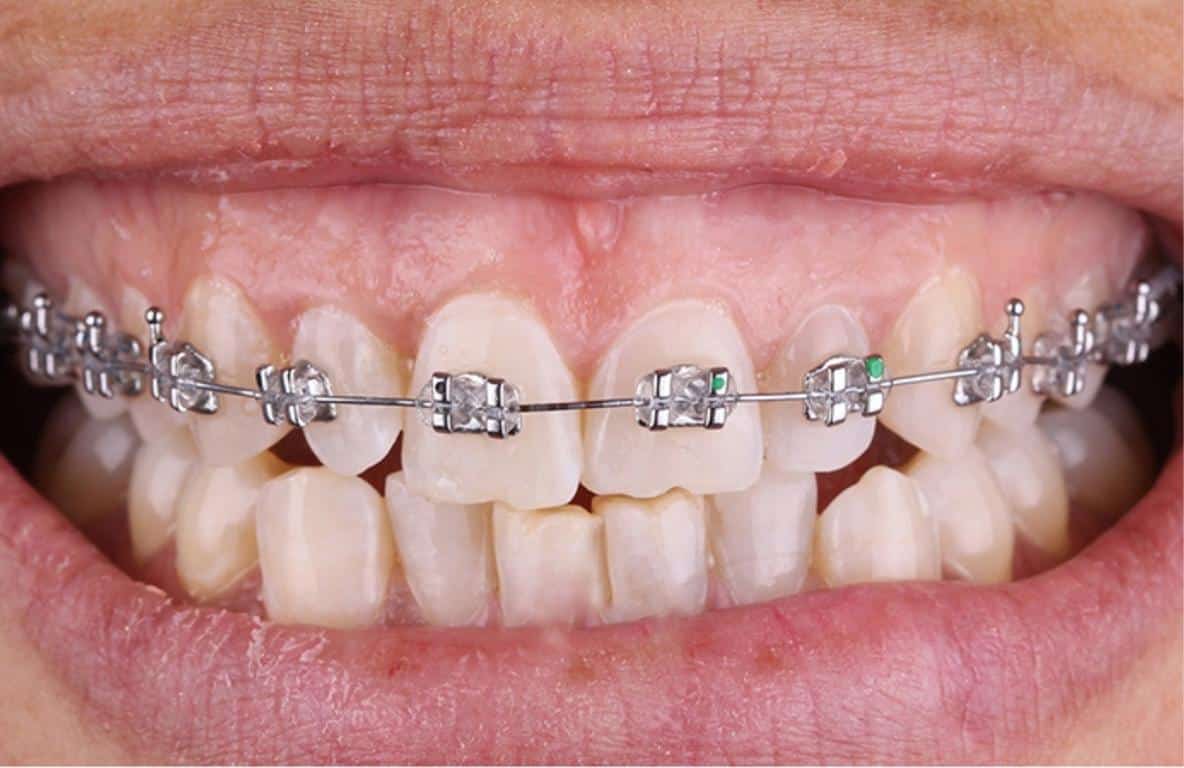

Ortodonti

Ortodonti yani diş teli uygulaması uyumsuz ve çarpık dişlerle, ağzı kapanış bozukluklarının nedenleri ve tedavisi ile ilgilenen anabilim dalıdır. Diş teli yani ortodonti tedavisi için diş hekiminizin ya da ortodontistinizin karar vermesi gereklidir.

Ortodonti Tedavisinde Kullanılan Araçlar Nelerdir?

- Sabit Ortodontik Araçlar